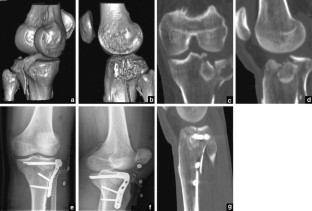

Fig. 1

Fig. 2